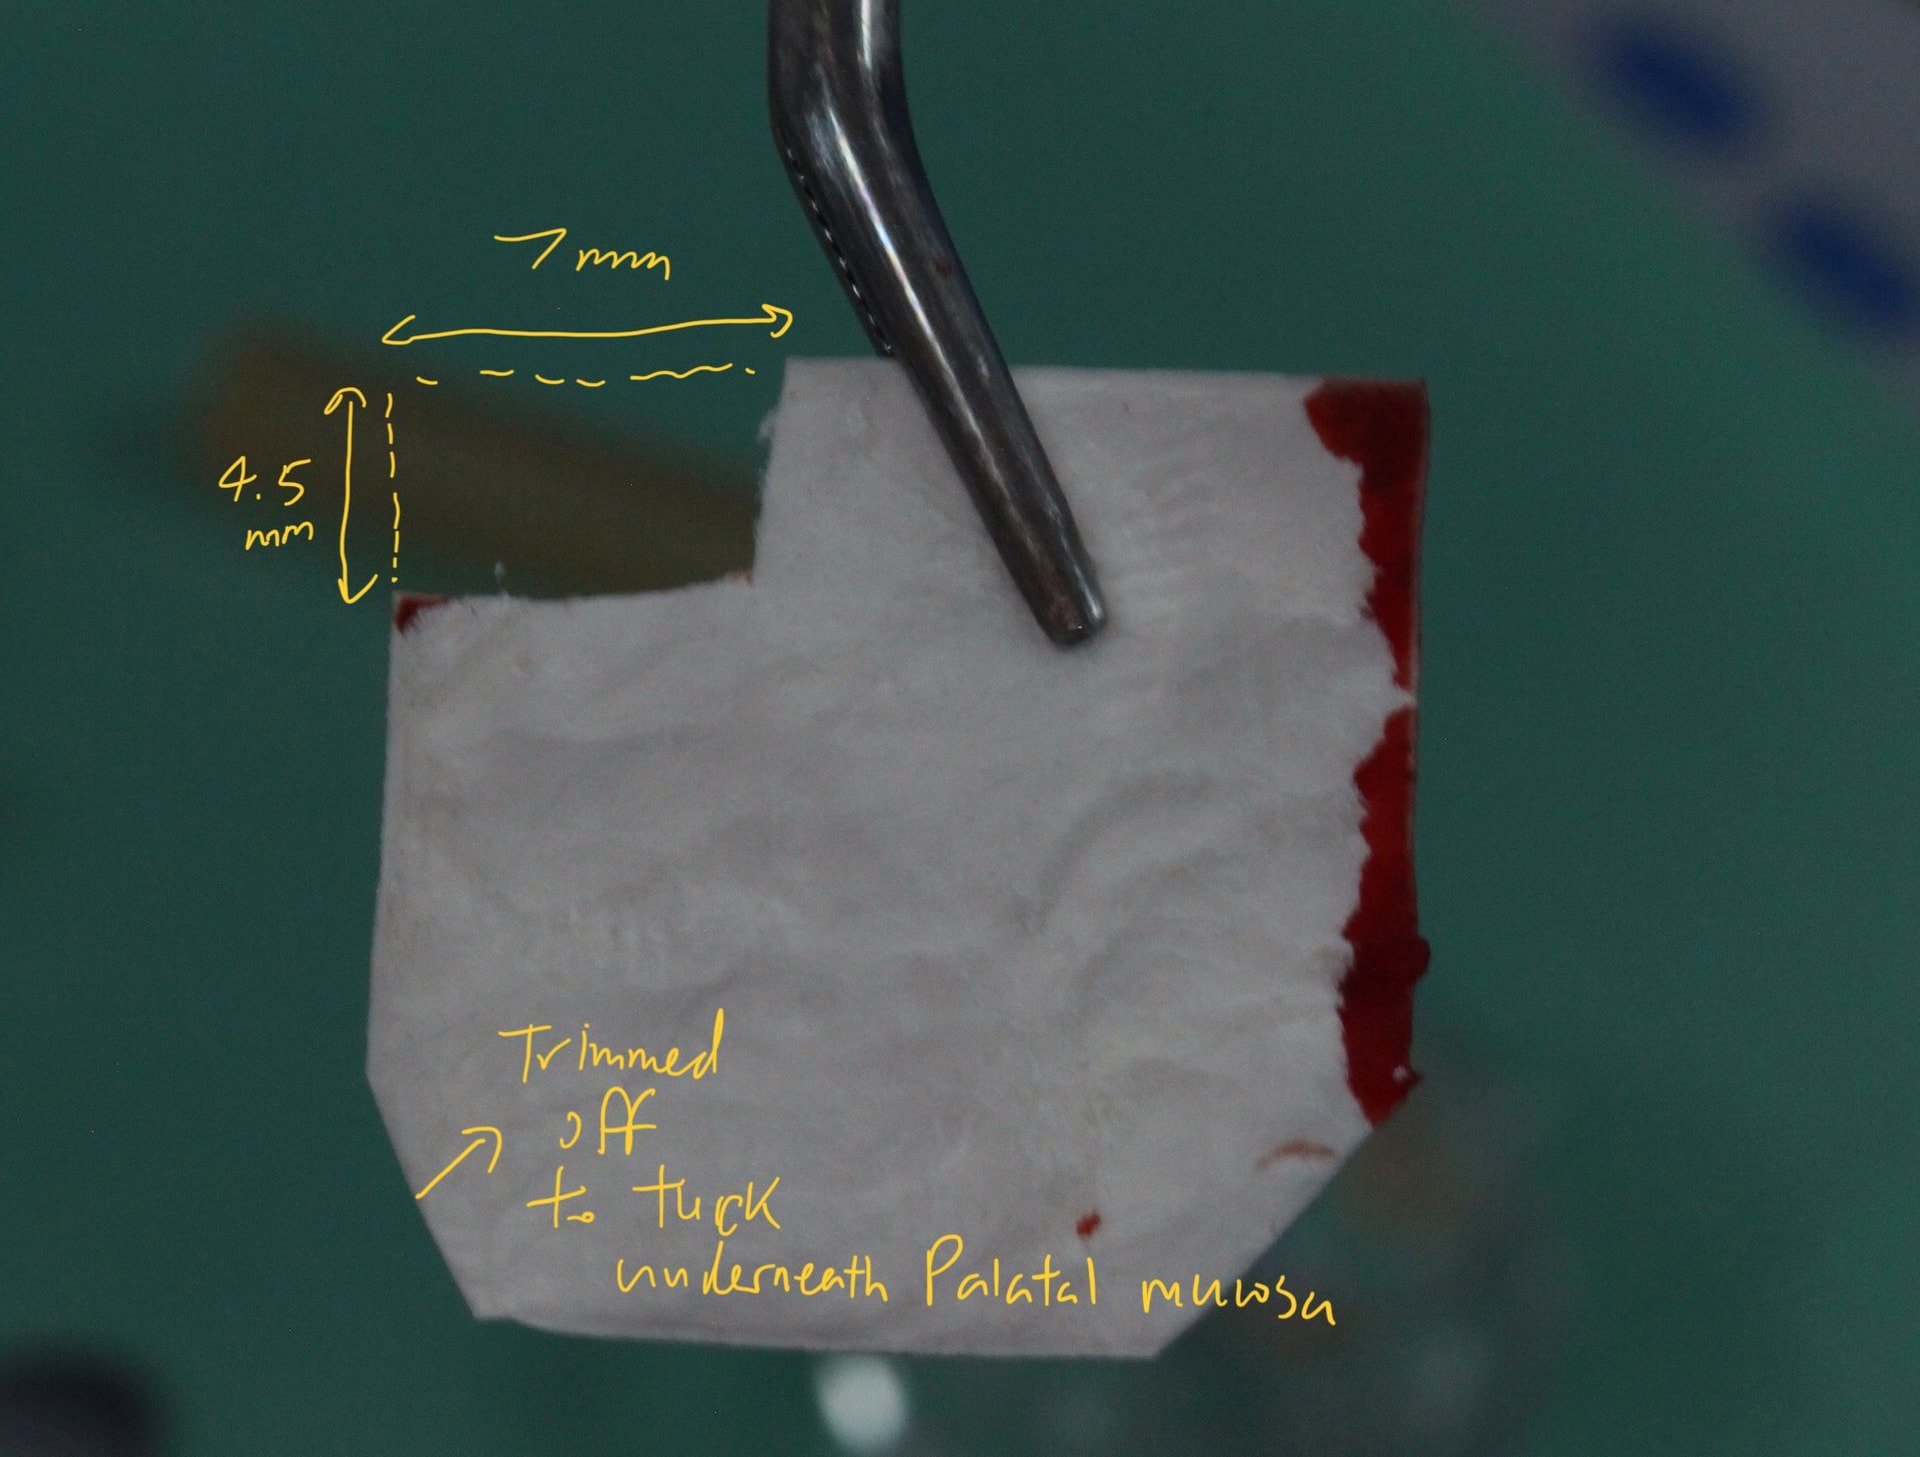

after degranulation bur and curettage of the socket, despite we had done similar things 2 months ago after XLA. there was oral astral communication with per formation of sinus membrane. the defect of the OAC is around 1-2mm, but the crestal defect is 4.5mm by 7mm wide as measured.

( I designed the bio guide dimension, not sure if 4.5mm by 7mm would be able to cover the OAC defect, which is much smaller at the base of the UR6 socket)